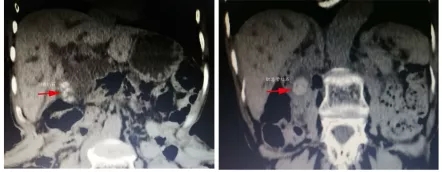

患者朱老太今年70岁,患有胆总管及胆囊结石多年,而胆绞痛、胆管炎反复发作导致朱老太苦不堪言、生活受到严重影响。

但是祸不单行,大约5年前干农活时腰背部受到撞击、因家境困难,又延误了治疗,朱老太逐渐出现驼背侧弯畸形,且日趋严重,而可恶的胆绞痛、胆管炎发作仍不期而至。

附属医院肝胆胰外科主任陈谦召集本科室、麻醉科及外科ICU专家一起参加术前讨论,仔细分析了患者病情,考虑到患者状况差,营养不良,体重仅有28kg,而胆管炎随时可能导致感染性休克等严重并发症发生,手术早期实施较好,但这意味着患者术前无充分时间营养支持等处理,由此也增加了患者麻醉手术及恢复风险。